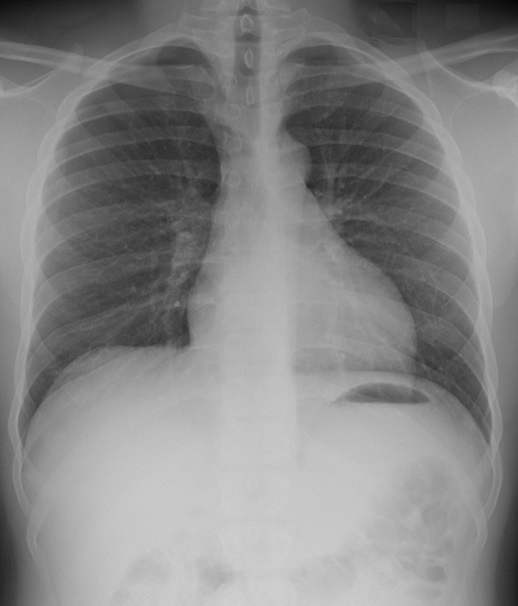

Aspect

radiologique d'une pneumothorax à petit

volume du pomon droit . Cliche de face

PA en inspiration |

|

Meme cas à

exposant au temps de expiration . On

peut en s'observe le pneumothorax à

petit volume collecte à l'apex et à

region axillaire droit du poumon |